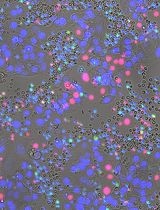

Neonatal ROSAmT/mG;Tie2-Cre mice of both sexes were used to visualize the hemodynamics of small intestinal microcirculation and leukocyte movement. Table 1 shows a comprehensive list of transgenic mouse lines carrying fluorescent reporters that could be used in this protocol. Alternative transgenic reporter lines expressing fluorescent proteins can also be used in this method.

| GFP mouse | C57BL/6 | Tg(CAG-EGFP) | Chicken β-Actin and cytomegalovirus enhancer | All tissues except for erythrocytes and hair appear green under excitation light. |

| mTmG mouse | C57BL/6 | RosamTmG | Chicken β-Actin/pCA | These mice possess loxP sites on either side of a membrane-targeted tdTomato (mT) cassette and express strong red fluorescence in all tissues and cell types examined. When bred to Cre recombinase expressing mice, the resulting offspring have the mT cassette deleted in the Cre expressing tissue(s), allowing expression of the membrane-targeted EGFP (mG) cassette located just downstream. |

| Tie2 Cre | (C57BL/6 x SJL)F1 | Tek-cre | Tek, endothelial-specific receptor tyrosine kinase | These transgenic mice express Cre recombinase under the control of a mouse Tek promoter and enhancer. This promoter is active in endothelial cells. |